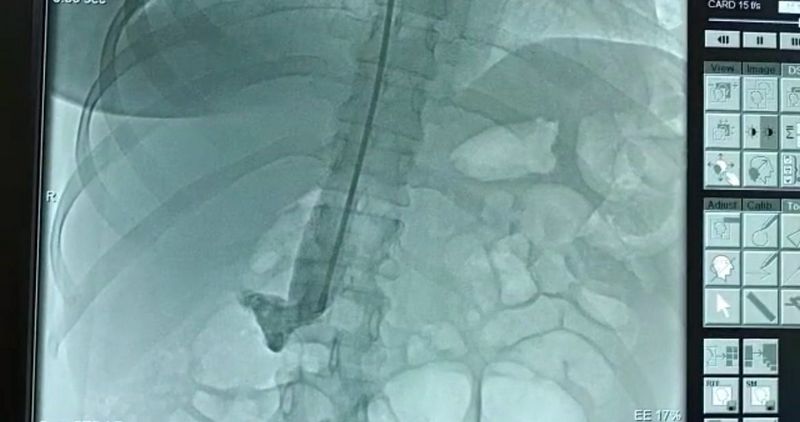

По данным пресс-службы Мангистауской областной больницы, у недавно родившей женщины диагностировали острый глубокий сосудистый тромбоз левой голени с признаками флотации.

- Если бы пациентка промедлила с обращением к врачам, могли быть серьезные последствия вплоть до наступления тромбоэмболии. Врачи вовремя предотвратили заболевание, установив кава-фильтр в нижнюю полую вену. Операция прошла успешно, - констатировал врач-кардиохирург Ернур Ордабаев.

- Тромб, образовавшийся в глубоких венах голени, может с током крови переместиться в легочную артерию, вызвав частичное или полное нарушение кровотока в ней. В такой ситуации человек умирает. Поэтому мы установили кава-фильтр и снизили уровень угрозы заболевания тромбоэмболией, - пояснил врач.

Операция длилась порядка 15 минут. Вместе с врачом-кардиохирургом Ернуром Ордабаевым ее проводил интервенционный кардиолог, аритмолог Курбанали Сабдинов.